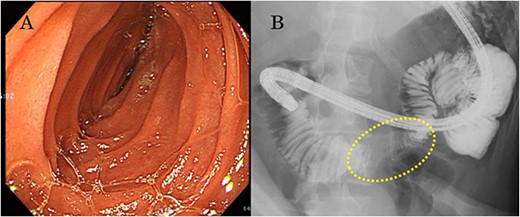

A 22-year-old man was referred to our department with the chief complaint of nausea and vomiting. An abdominal examination revealed a mass with poor mobility and elastic hardness on the right side of the navel. Further evaluations using abdominal ultrasonography revealed an ~83 × 51 × 49 mm well-defined, oval, hypoechoic, and heterogeneously enhanced mass with a strong echo. A contrast-enhanced computed tomography scan showed a well-defined, heterogeneous enhancement with calcification. The tumor pushing the transverse part of the duodenum was present on the ventral ileocolic vessels and measured ~6 cm (Fig. 1). Magnetic resonance imaging was performed to confirm invasion of other organs. All of the above examinations suggested that the tumor had not invaded other organs, especially the duodenum. Esophagogastroduodenoscopy revealed no lesions in the duodenal lumen. However, the duodenum was pushed by a mass outside the lumen (Fig. 2).

(a) Esophagogastroduodenoscopy reveals no lesion in the duodenal lumen, but the transverse duodenum is pushed by the mass from outside the lumen; (b) upper gastrointestinal examination illustrates that the transverse duodenum is pressed by the mass palpable outside the body of the patient.